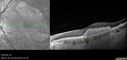

Multifocal Vitelliform Macular Dystrophy422 views58 year old female with mild vision loss - 20/20 OU - extensive testing has shown no cancer. Case of Karina Findlay, MD